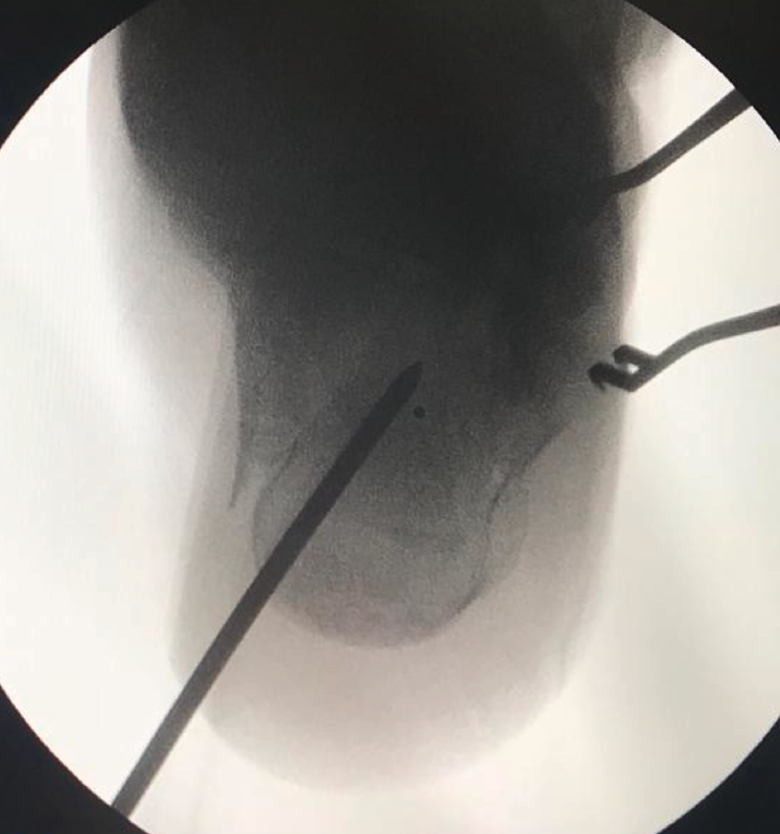

A la hora de corregir el varo-valgo y la longitud del calcáneo colocamos un pin Steinmann o aK de 3,0 o 4,0 en la tuberosidad posterior y damos angulación varo o valgo (Figura 4) según necesite cada caso y siempre comprobando con la fluoroscopia (proyección axial). Una vez conseguida la angulación correcta, se fija de forma definitiva con 2 tornillos canulados de posterior a anterior (Figuras 5 y 6).

Figura 4. Proyección axial del calcáneo. Steinmann en la tuberosidad posterior para corregir el varo-valgo.